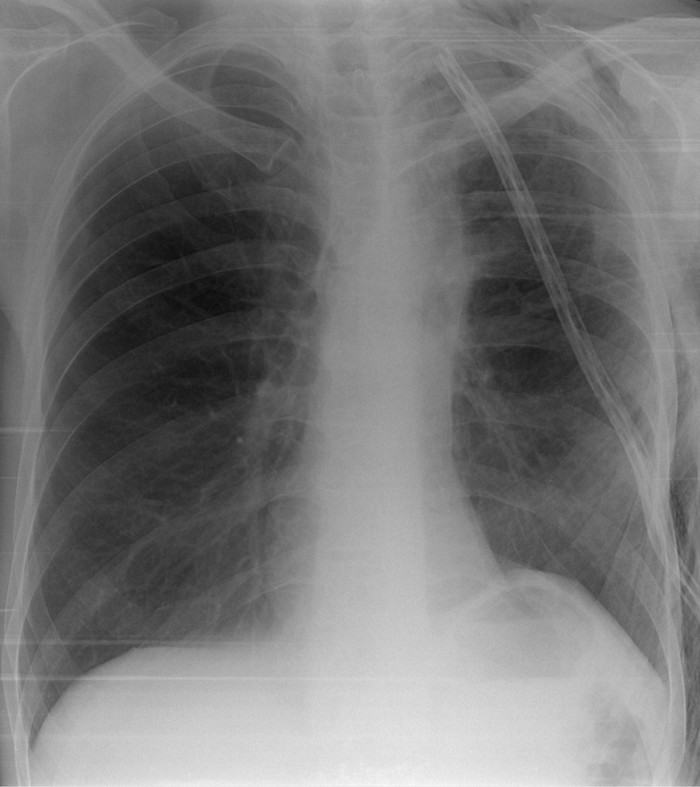

Если б не дренаж, установленный во время операции, то по рентгену вообще сложновато сказать с какой стороны была операция (шутка). Нижняя доля левого лёгкого расправилась, полностью заняла освободившийся после удаления соседней доли: